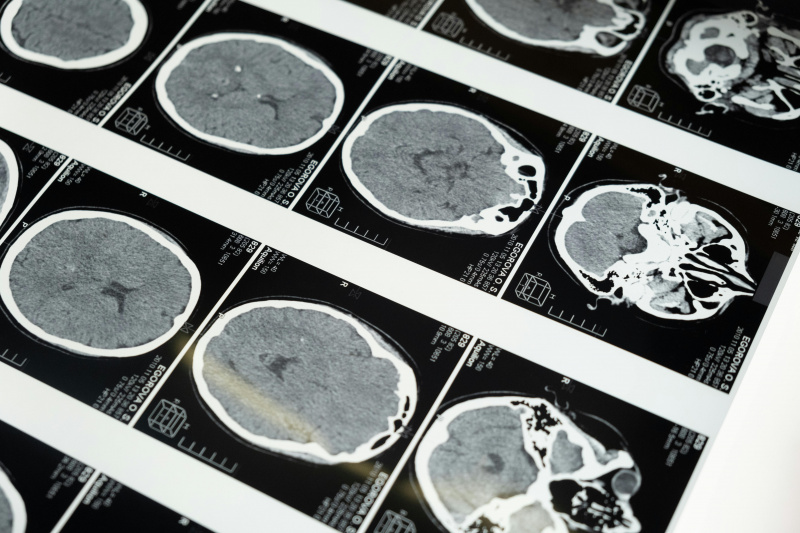

When someone experiences a concussion, also known as a mild traumatic brain injury (mTBI), the damage is not always apparent through symptoms. Instead, much of the injury occurs on a chemical level inside the brain. After the initial impact, researchers have observed multiple pathologies to TBIs, including ionic flux, glutamate release, energy crisis, cytoskeletal damage, axonal dysfunction, and altered neurotransmission.[1] To read more about these processes, click here. One of the most important pathologies involved is neuroinflammation.